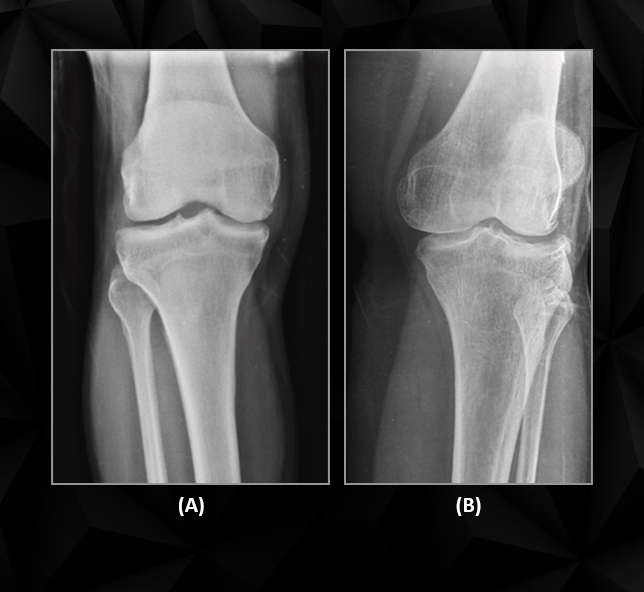

The gold standard for diagnosing osteoporosis has long been DEXA (Dual-Energy X-ray Absorptiometry) scans. While accurate, DEXA scans are expensive, require specialized equipment, and are often inaccessible to patients in underserved communities. Manual interpretation of X-rays, another commonly used method, is highly dependent on the availability of trained radiologists and can take up to 10 minutes per image, leading to delays in diagnosis and treatment. For high-volume healthcare facilities, these inefficiencies can result in a 25% reduction in overall diagnostic throughput, leaving both patients and providers at a disadvantage.

Despite advancements in medical technology, the diagnosis and management of osteoporosis remain fraught with challenges. The World Health Organization identifies osteoporosis as a public health crisis, with over 8.9 million fractures annually attributed to the condition. CareVision Diagnostics, as the diagnostic backbone of a leading multi-specialty hospital, faced several critical challenges in delivering timely and accurate diagnostics across departments, from orthopedics to geriatrics.

Manual X-ray interpretation adds an average of 10 minutes per patient, creating bottlenecks in high-demand facilities.

Objective: Automate X-ray analysis for faster and more accurate osteoporosis detection.